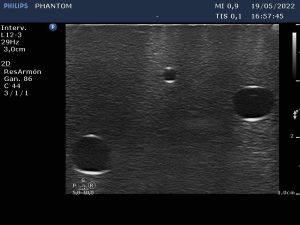

És per això que aquest mes de juny ha arrencat amb un ‘Curs de punció ecoguiada i dispositius d’accés vascular’, al Consell Comarcal de l’Alt Urgell, impartit per tres infermers, que a més són tècnics superiors en Imatge pel Diagnòstic, membres de l’Equip de Teràpia Intravenosa (ETI) de l’Hospital Universitari Arnau de Vilanova (HUAV) de Lleida. La punció ecoguiada és una tècnica gens invasiva que permet a la infermera veure, de forma clara i directa, l’estructura vascular a la qual ha d’accedir i col·locar l’agulla en el lloc més adient per inserir la via (catèter) o qualsevol altre dispositiu d’accés vascular (DAV), evitant incomoditats i complicacions pel pacient.

Alejandro Bergua, Jordi Farrero i Ferran Padilla han ofert dues sessions (dies 1 i 2 de juny) sobre les tècniques més eficients de punció ecoguiada: inserció i principals dispositius d’accés vascular o el manteniment i cures bàsiques associades, han centrat el programa que també ha ofert formació teòrica i pràctica sobre els equips i aparatologia d’ecografia i la identificació dels diferents tipus d’accessos vasculars.

Amb aquest curs, el COILL pretén millorar la qualitat i atenció de les infermeres de les comarques pirinenques introduint-les en el Mètode RaPeVA, un mapeig venós en diversos passos establerts de forma lògica i progressiva per analitzar les estructures internes del braç, descartar les zones de risc, determinar el lloc més apropiat de punció i assegurar-se la viabilitat de tot el recorregut del catèter.